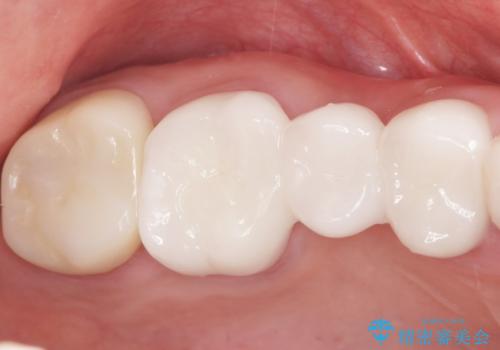

患者様のご希望により、金属を使わないオールセラミックのブリッジによる補綴治療を行いました。

金属の土台も除去し、ファイバーコア(金属を使わない強度のあるしなやかな土台)へやりかえました。

自然な仕上がりと咬み心地に喜んで頂けました。

クラウンの種類:オールセラミッククラウン スタンダード